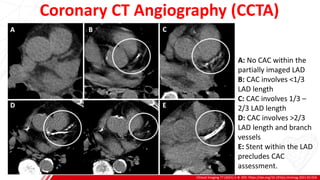

Coronary CT Angiography (CCTA)

Clinical Imaging 77 (2021) 1–8. DOI: https://doi.org/10.1016/j.clinimag.2021.02.016

A: No CAC within the

partially imaged LAD

B: CAC involves <1/3

LAD length

C: CAC involves 1/3 –

2/3 LAD length

D: CAC involves >2/3

LAD length and branch

vessels

E: Stent within the LAD

precludes CAC

assessment.